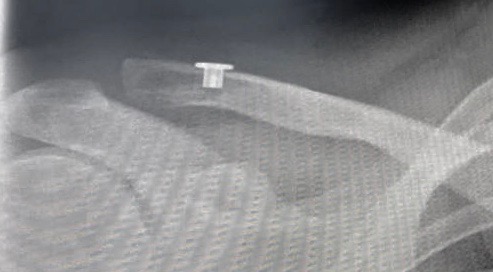

La chirurgie se déroule en ambulatoire sous anesthésie générale et locorégionale. Elle est effectuée sous arthroscopie ou à ciel ouvert. En aiguë, le principe de la chirurgie est la stabilisation de l’articulation acromioclaviculaire grâce à un système d’endobouton. Il est parfois nécessaire de protéger la réduction articulaire par une ostéosynthèse temporaire (broches et fil métallique) ou par la suture directe du ligament acromioclaviculaire et de la chappe musculaire. Dans les cas de lésions chroniques, instables et sans arthrose acromio-claviculaire, le principe est de réduire et stabiliser temporairement la luxation grâce à une ligamentoplastie